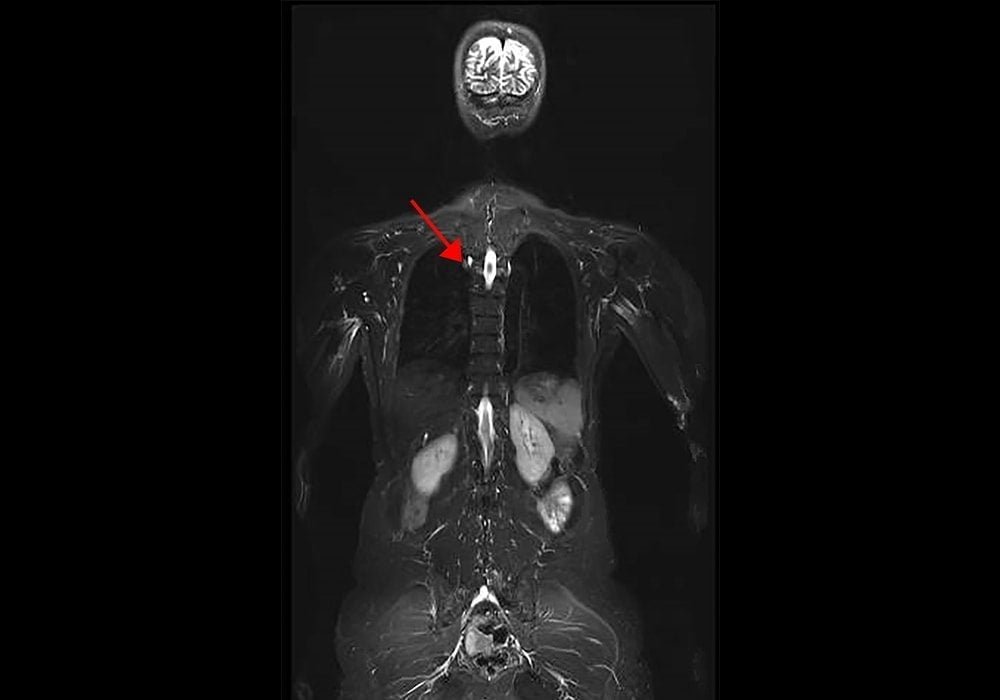

Sumber foto: NIH Image Gallery / Flickr

Penjelasan foto: dalam sebuah studi baru dari National Cancer Institute (NCI), bagian dari National Institutes of Health, para peneliti menemukan prevalensi kanker yang lebih tinggi dari yang diharapkan pada skrining awal pada individu dengan sindrom Li-Fraumeni (LFS), kelainan bawaan langka yang menyebabkan untuk risiko lebih tinggi terkena kanker tertentu. Penelitian ini menunjukkan kelayakan protokol skrining kanker baru yang komprehensif untuk populasi berisiko tinggi ini.

Gambar ini adalah bagian dari gambar representatif dari MRI seluruh tubuh pasien LFS. Panah menunjukkan lesi yang ditemukan sebagai adenokarsinoma paru.

Kredit foto: National Cancer Institute, NIH